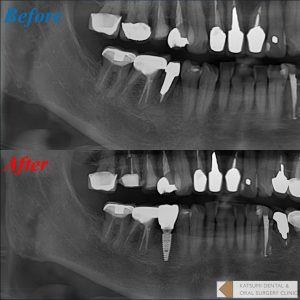

右下5番が保存不可能と言われ、インプラントを希望するも前医では骨がないためできないと断られたため当院へ来院された患者さん。同歯は歯根が露出し骨が欠損している状態。抜歯後も骨欠損に伴い顎堤も大きく陥凹。インプラント周囲に明らかに骨が不足するため、インプラント埋入と同時にGBR法による骨移植術を併用しました。GBR法とは、骨欠損部に骨補填材を充填し、メンブレンという膜で被覆することによって周囲軟組織の侵入を遮断し、骨の再生を図る術式です。当院では更にAFG(Autorogous Fibrinogen Glue)という血液の再生療法を併用しております。インプラント埋入が達成すると共に、歯肉の形態も良好であることはお分かりになると思います。